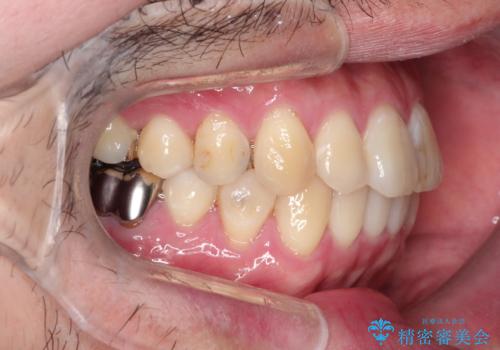

全体的ながたつきをインビザラインで改善

- 全体的ながたつきを主訴に来院されました。

歯と歯の間をわずかに削って、スペースをつくり並べる計画としました。

しっかりと、マウスピースの装着時間を守っていただいたので、スムーズに治療をおえることができました。